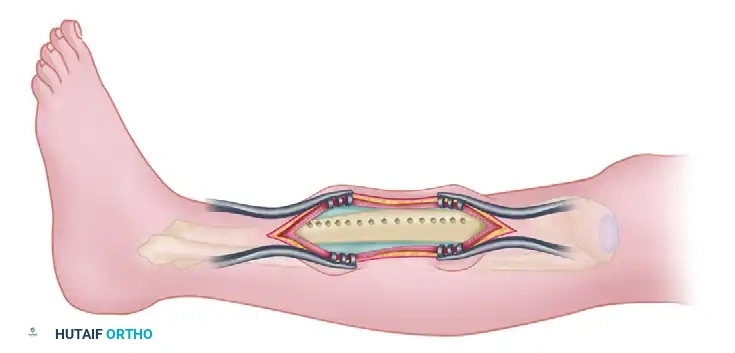

This highly specialized technique involves transecting the malunited segment perpendicular to the normal diaphysis both proximally and distally. The intercalary malunited segment is then split longitudinally and wedged open—much like a clamshell—allowing an intramedullary (IM) rod to pass through. This anatomically aligns the proximal and distal segments of the diaphysis while utilizing the expanded intercalary segment as a biological sleeve. The technique provides robust mechanical stability, restores length and alignment, and leverages the osteogenic potential of intramedullary reamings.

- Guidewire Passage: Place the limb over a radiolucent triangle. Under fluoroscopic guidance, pass the ball-tipped guidewire from the proximal tibial segment, through the opened clamshell osteotomized segment, and into the distal segment.

- Verification: Measure the length of the guidewire. Confirm on both AP and lateral fluoroscopic images that the entrance angle and the ending point in the distal segment are perfectly centered in the medullary canal.

- Nail Insertion: Pass the selected intramedullary rod and accomplish proximal interlocking.

- Positioning for Correction: Remove the targeting jig from the proximal aspect of the tibial nail. Remove the limb from the radiolucent triangle and place it flat on the operating table. At this stage, the sagittal and coronal plane corrections are intrinsically achieved by the straight IM nail passing through the realigned segments.

- Length and Rotation: Only length and rotation remain to be corrected. Have an assistant apply manual traction, or utilize a femoral distractor/external fixator to dial in the exact length and rotation. Compare clinically with the contralateral draped limb.

- Distal Interlocking: Once perfect length and rotation are achieved, place the distal interlocking bolts using a freehand fluoroscopic technique.